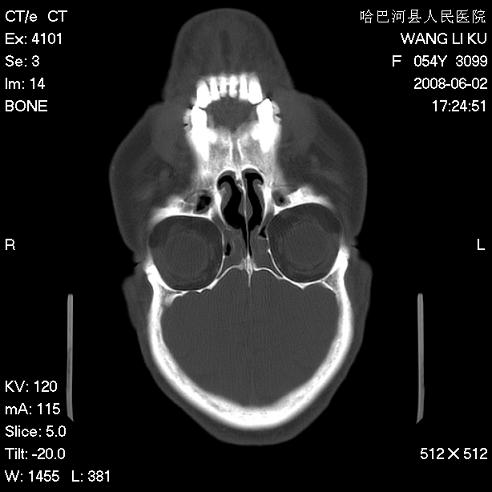

标题: CT13803:反复性鼻塞、流涕一年余 [打印本页]

标题: CT13803:反复性鼻塞、流涕一年余

副鼻窦炎,右上额窦积脓。左眼肌锥内见致密影,视神經受压

1.全组副鼻窦炎2.双侧上颌窦积液

全组副鼻窦炎 肌锥内高密度灶。建议进一步检察检查

1、全组副鼻窦炎。

2、左眼眶肌锥内病变,小血管瘤?建议增强。

1)全副鼻窦炎(左侧上颌窦黏膜下囊肿或息肉)。2)左眼眶肌锥内不规则小结节状软组织密度影;考虑为小血管瘤可能。建议行ct增强扫描检查。

全组副鼻窦炎,左侧肌锥内不规则形软组织肿块影,与眼外肌密度相当,左侧视神经受压,肿块与视神经及眼外肌分界清晰,眼外肌无增粗,眶壁无破坏,球后脂肪间隙不模糊,考虑良性改变,小血管瘤或神经源性肿瘤可能,建议增强扫描。

谢谢,增强扫描做了,眶内病灶与海绵窦同步明显强化,血管瘤